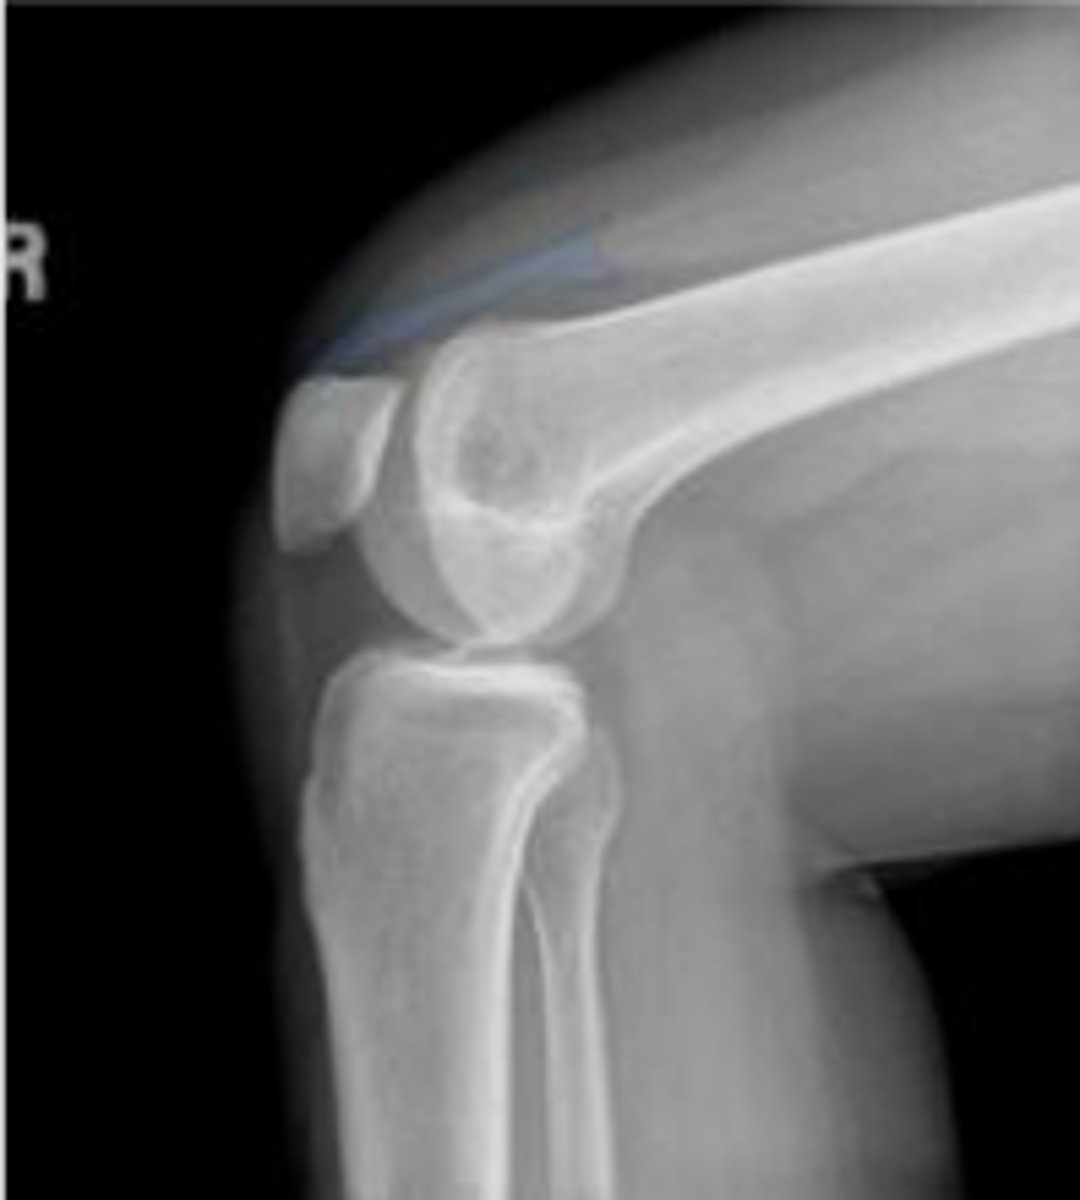

Right lateral knee

What is the name of the radiographic view?

Right patellofemoral joint space

What joint space is the arrowing pointing to?

Right patellar ligament

What is outlined?

Right quadriceps tendon

Hoffa's fat pad of the right knee

Lipohemarthrosis

What are the arrows pointing to?